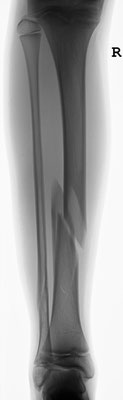

14- jähriger Junge mit Unterschenkelbruch. Minimal-invasive Stabilisierung mit Markdrähten. Das Bein kann bei optimaler Anwendung der Drähte bereits nach einer Woche mit 15 kg an Gehstützen belastet werden.